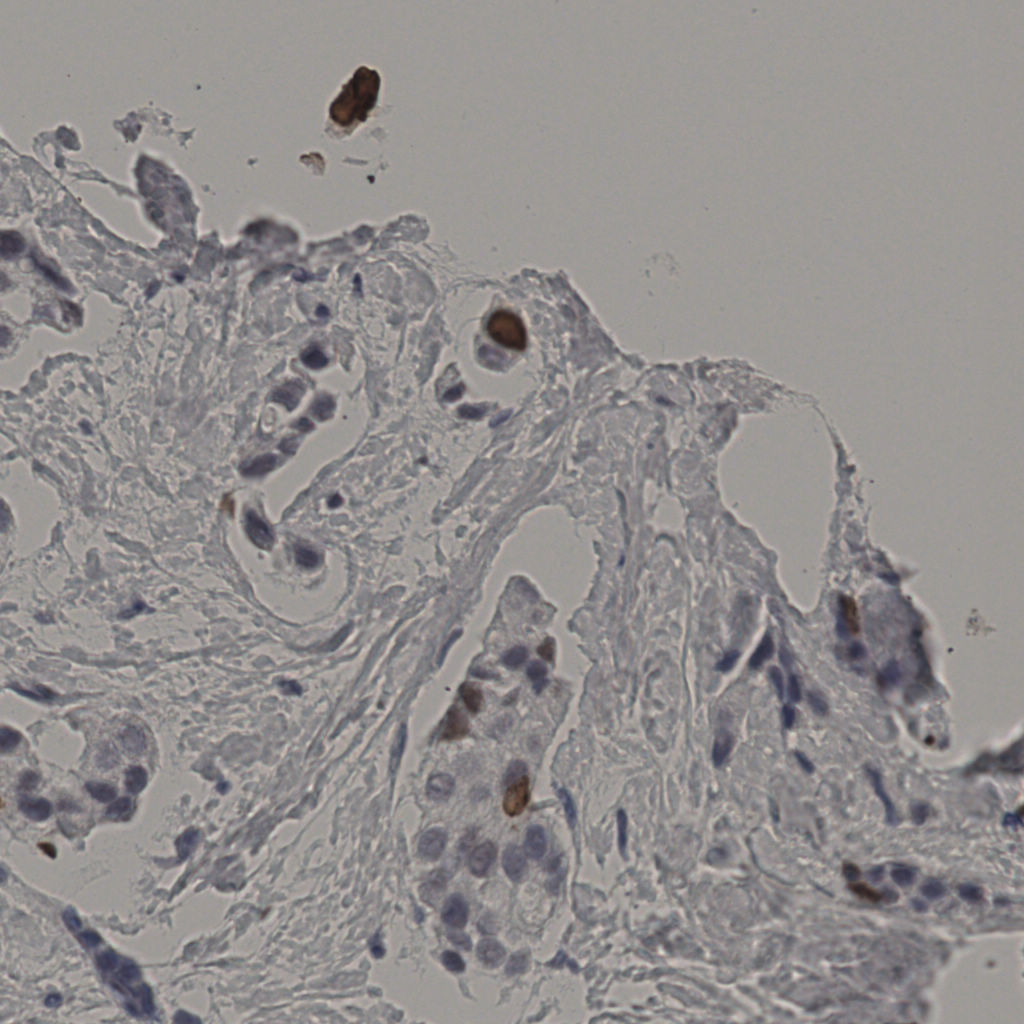

缩略图

标记后

标记前